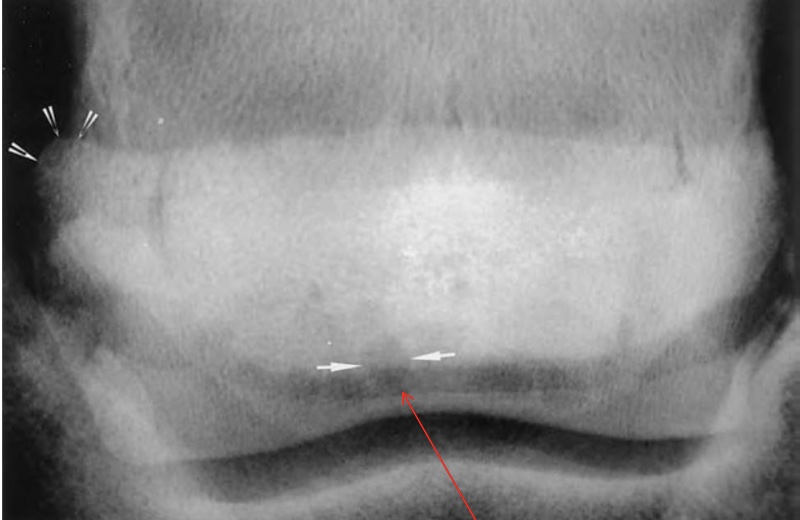

what is this

a- normal

b- navicular dz w/ synovial invaginations (lollipops)

left vs right images

left: normal

right: navicular disease with loss of medullar architecture and increased synovial invaginations (lollipops) and damaged flexor surface (loss of mineralization)

what is this

arrow on left- enthesiophyte (rounded edge)

arrow on bottom- synovial invaginations

what is arrow pointing at on MRI

edema of the navicular bone

white spots on mri are indicative of pathology (bc of fluid, inflammation)